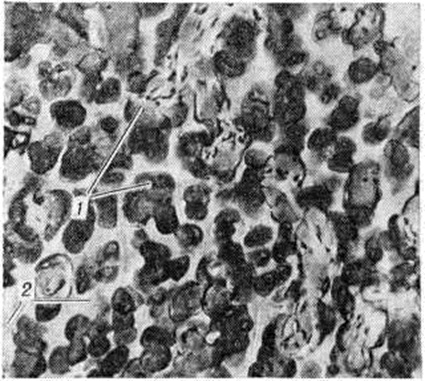

Рис. 1.

Микропрепарат позвонка при мраморной болезни (зона энхондрального око стенения); образование костных перекладин из основного вещества хряща: 1 — образующиеся костные перекладины, 2 — дугообразные линии склеивания.

При микроскопическом исследовании обнаруживается, что патологический избыточное костеобразование идёт во всех костях скелета как в области эпифизарного хряща (ростковой зоны), так и по ходу диафиза. Очень редко наблюдается периостальное костеобразование. В костномозговых пространствах в некоторых случаях обнаруживают толстые слоистые структуры, располагающиеся вокруг капилляров и представляющие собой патологический остеоны. В других случаях костномозговые пространства бывают выполнены пластинчатой костной тканью с многочисленными дугообразными линиями склеивания. Встречаются балки из незрелой грубоволокнистой костной ткани. В пластинчатой кости уменьшено количество остеобластов, распределение их в костной ткани неравномерное. Явлений резорбции кости почти не наблюдается. Костномозговые пространства резко сужены, выполнены фиброретикулярной тканью. Лишь местами можно встретить участки костного мозга. В зоне энхондрального окостенения основная субстанция хряща не подвергается резорбции, как это имеет место в физиологический условиях, а даёт образование костной ткани, сначала в виде округлых островков (рисунок 1), а затем широких костных перекладин, по краям которых видны остатки основной субстанции хряща. По мере удаления от эпифизарного хряща вещество кости приобретает пластинчатое строение (рисунок 2).